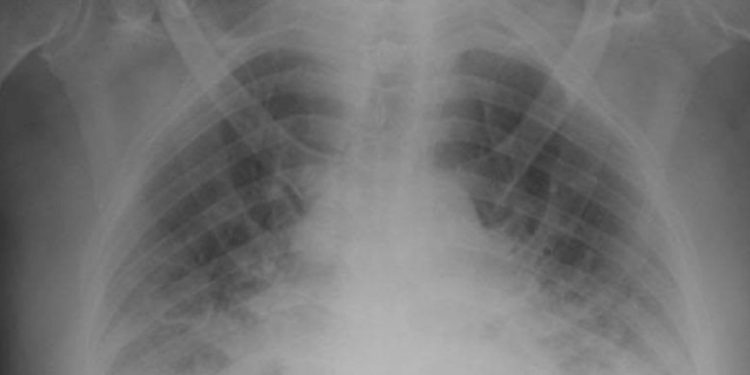

Los doctores también indicaron que, debido a la falta de instalaciones sanitarias en su localidad, el hombre tardó una semana en ser trasladado a un hospital de la capital. Además, puntualizaron que, en el momento de su llegada a urgencias, estaba consciente, pero observaron que tenía múltiples lesiones en todo el cuerpo. Los resultados de los análisis clínicos y de laboratorio revelaron varias condiciones bioquímicas críticas en hígado y páncreas y una lesión renal aguda. Además, una radiografía de tórax mostró un edema pulmonar.